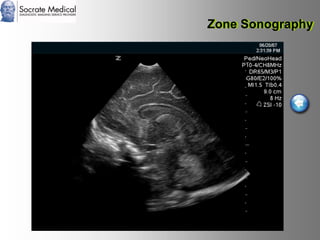

Il documento presenta la tecnologia della zone sonography, che promette una rivoluzione nel campo degli ultrasuoni, superando i limiti dei sistemi tradizionali grazie a metodi di acquisizione dati più veloci e una gestione delle informazioni migliorata. Questa tecnologia consente una maggiore definizione dell'immagine, una riduzione degli artefatti e un'ottimizzazione del processo diagnostico, con vantaggi in termini di tempo e costi. Inoltre, il channel domain processing e la zone speed technology offrono applicazioni avanzate e miglioramenti nella sicurezza diagnostica.